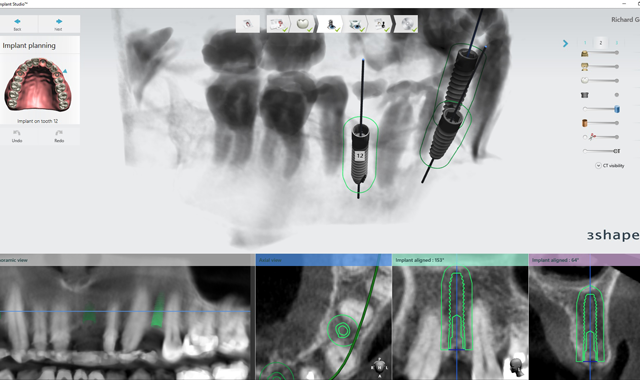

2. This patient was then scanned with a 3Shape TRIOS intraoral scanner. The resulting color scan is shown in Figure 3. This scan was then pulled into 3Shape Implant Studio and aligned with the DICOM data, and placement of three BioHorizons Implants was planned. Tooth position #12 was planned with a 3.0 mm x 15.0 mm implant. In Figure 4 you can see the root formations for teeth 11 and 13 created a limited space situation.

Fig. 3 Fig. 4